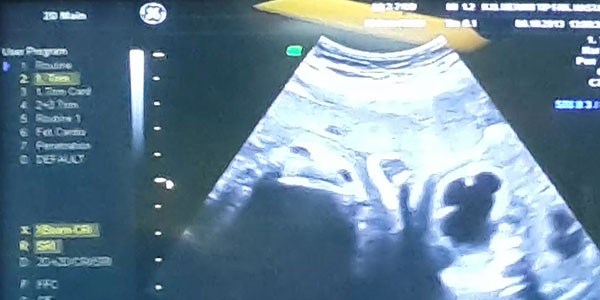

Konya'da idrar torbası şişen, böbreklerinde genişleme görülen anne karnındaki 4 aylık bebeğe hayati bir operasyon gerçekleştirildi.

Konya'da idrar yolları kapalı olduğu için idrar torbası şişen, böbreklerinde genişleme meydana gelen ve yaşamını sağlayan etrafındaki su biten anne karnındaki böbrek hastası 4 aylık bebeğe, operasyon gerçekleştirildi. Hayatta kalabilmesi için idrar torbasıyla bebeğin sıvısı etrafındaki bölgeye yerleştirilen şantla böbrekleri rahatlatılan bebek yaşatıldı.

Acar, yapılan kontrollerde bebeğe anne karnındayken müdahale kararı aldı. Bebek küçük olduğu için oldukça riskli olan böbrek ameliyatı, Acar ve ekibi tarafından başarıyla gerçekleştirildi.

Hayati operasyonla ilgili, AA muhabirine bilgi veren Acar, bebeğin idrar torbasında aşırı şişlik, etrafında suyunun olmaması, buna bağlı olarak böbreklerinde aşırı genişleme olduğunun tespit edildiğini söyledi.

Sadece 400 gram ağırlığında, 20 santimetre boyundaydı

"Ameliyatın özelliği; önce anne karnına giriyorsunuz. Annenin cilt altı karın boşluğundan rahime giriyorsunuz. Rahimden sonra çocuğun idrar torbasının olduğu bölgeye girilip, idrar torbasıyla çocuğun sıvısı etrafındaki bölgeye şant yerleştiriliyor. Bu şekilde idrar torbasından dışarıya geçemeyen sıvı, rahim etrafındaki sıvıyla yoğunlaştırılıyor, böbrekler bu şekilde rahatlatılıyor" diyen Acar, şöyle devam etti:

"Alerji yapmayan 5-6 santimetre uzunluğunda, 1 milimetre genişliğinde malzeme kullanıldı. Bu, annenin dokularına ve çocuğa takılmayacak şekilde direkt olarak idrar torbasına yerleştiriliyor. Hastaların yarısından çoğunda iyi netice alınıyor. Anne karnında ameliyat olduğu için zorluğu olan bir operasyondu. Bebek çok küçük olduğu için ameliyat zordu. İdrar yolları kapalı olduğundan, idrar torbası ve böbrekler su topluyordu. Zaten bu tür hastaların özelliği; tedavi edilmezse bir süre sonra böbrek yetmezliğine gidiyor, ya anne karnında kaybediliyor ya da böbrek yetmezliğiyle doğuyor. Sonuçta bu hastaların doğduğu zaman da tedavilerine devam edilmeli, kapalı idrar yolları açılmalıdır. Bunlar risk grubuna giren hastalar. Bebek 350-400 gram ağırlığında, boyu 20 santimetre civarındaydı. Bu kadar küçük hastaya başarılı bir operasyon gerçekleştirdik."